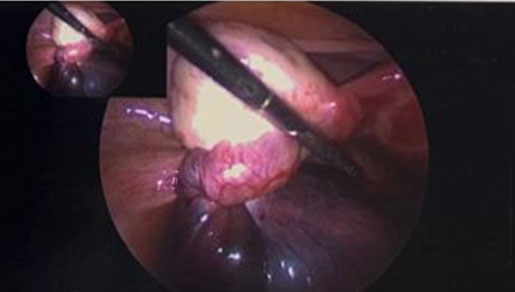

The gynecology service was consulted and the patient was admitted for observation given her continued abdominal pain. Her pain did not improve, and she thus underwent diagnostic laparoscopy on hospital day two. On laparoscopic survey there was no evidence of adhesions or endometriosis. The left ovary was normal in appearance. The left fallopian tube, however, was noted to be enlarged to approximately 10 cm, dark purple in appearance and torsed three times as shown in Figure 5. The decision was made to perform a left salpingectomy due to tubal torsion. There were no complications with the procedure, estimated blood loss was less that 10 mL and the patient was discharged on postoperative day 0. The final pathology revealed tubal hemorrhage and necrosis consistent with tubal torsion.

Figure 5: Torsed left fallopian tube via laparoscopy (Case 2).